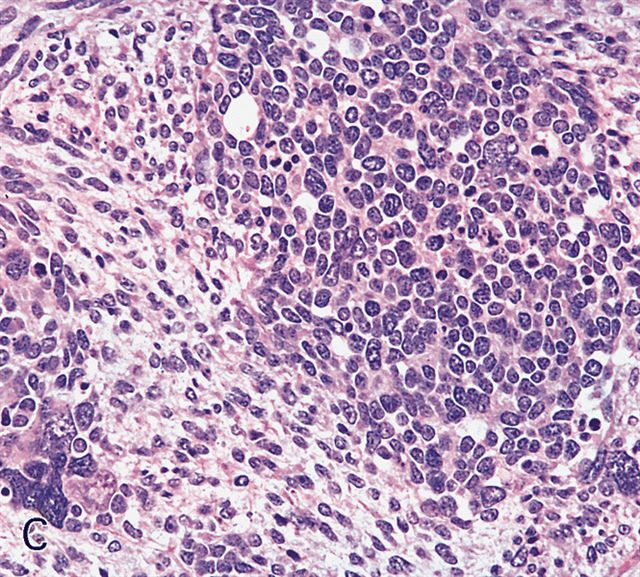

Contributed by Erdener Özer, M.D., Ph.D. and Mark R. Wick, M.D.

Contributed by Carolina Martinez Ciarpaglini, M.D., Ph.D. (Case #276) - tonsillar mass

Microscopic (histologic) description

- Composed of primitive mesenchymal cells that show variable degrees of skeletal muscle differentiation

- They are moderately cellular but in the typical pattern often contain both hypocellularity and hypercellular areas with a loose, myxoid stroma

- Perivascular condensations of tumor cells in the less cellular regions are common

- Sheets of small, stellate, spindled or round cells with scant or deeply eosinophilic cytoplasm and eccentric, small oval nuclei with a light chromatin pattern and inconspicuous nucleoli

- Cells are undifferentiated, round or spindled with minimal cytoplasm, frequent mitotic figures

- Deeper layers of the tumor are typically less cellular but overall conform to the histology of embryonal rhabdomyosarcoma (ERMS) with variation by region

AFIP images - botryoid variant